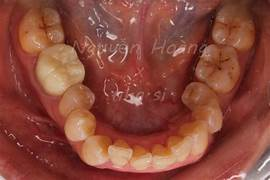

Cung răng là hình dạng cong của răng răng khi nhìn từ phía trước. Cung răng được hình thành nhờ sự sắp xếp của các răng trên cung hàm. Hình dạng cung răng rất đa dạng, phụ thuộc vào nhiều yếu tố như di chuyển, thói quen, và sự phát triển của xương hàm. Việc đánh giá cung răng là một phần quan trọng trong dự đoán và lập kế hoạch điều chỉnh khoa học, đặc biệt là trong nha chỉnh sửa.

Có nhiều cách phân loại cung răng, nhưng thường gặp nhất là dựa trên dạng hình:

- Cung răng hình parabol: Đây là hình dạng cung răng lý tưởng, với đường cong mềm mại và cân đối. Các răng được sắp xếp đều đều, không bị trôi lạc.

- Cung răng hình elip: Cung răng có dạng thon dài hơn so với cung răng parabol.

- Cung răng hình tam giác: Cung răng có hình dạng chu vi, không cân đối. Thường gặp ở các trường hợp xu hướng bị lệch hoặc thiếu răng.

- Cung răng vuông: Cung răng có hình dạng gần giống hình vuông, với các răng được sắp xếp thẳng hàng.